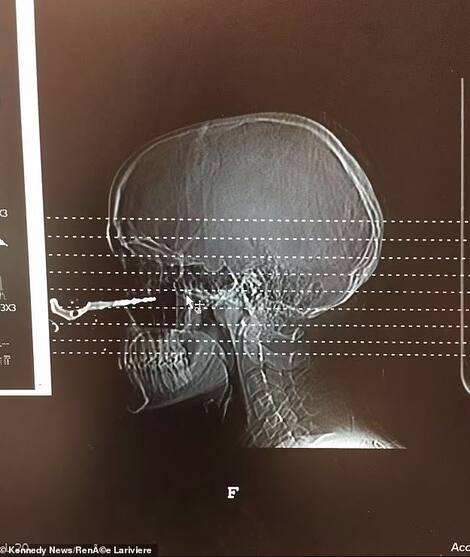

An Ontario woman feared for her life after a friend’s thrown car keys pierced her cheek near her eye.

Renée Lariviere, 24, tried to grab her car keys, but instead accidentally stuck them in an inch-and-a-half-deep nasal cavity.

Surgeons were able to extract the key from the cavity to suture the wound. Lucky for her misfortune, the young woman comes out without any scars.